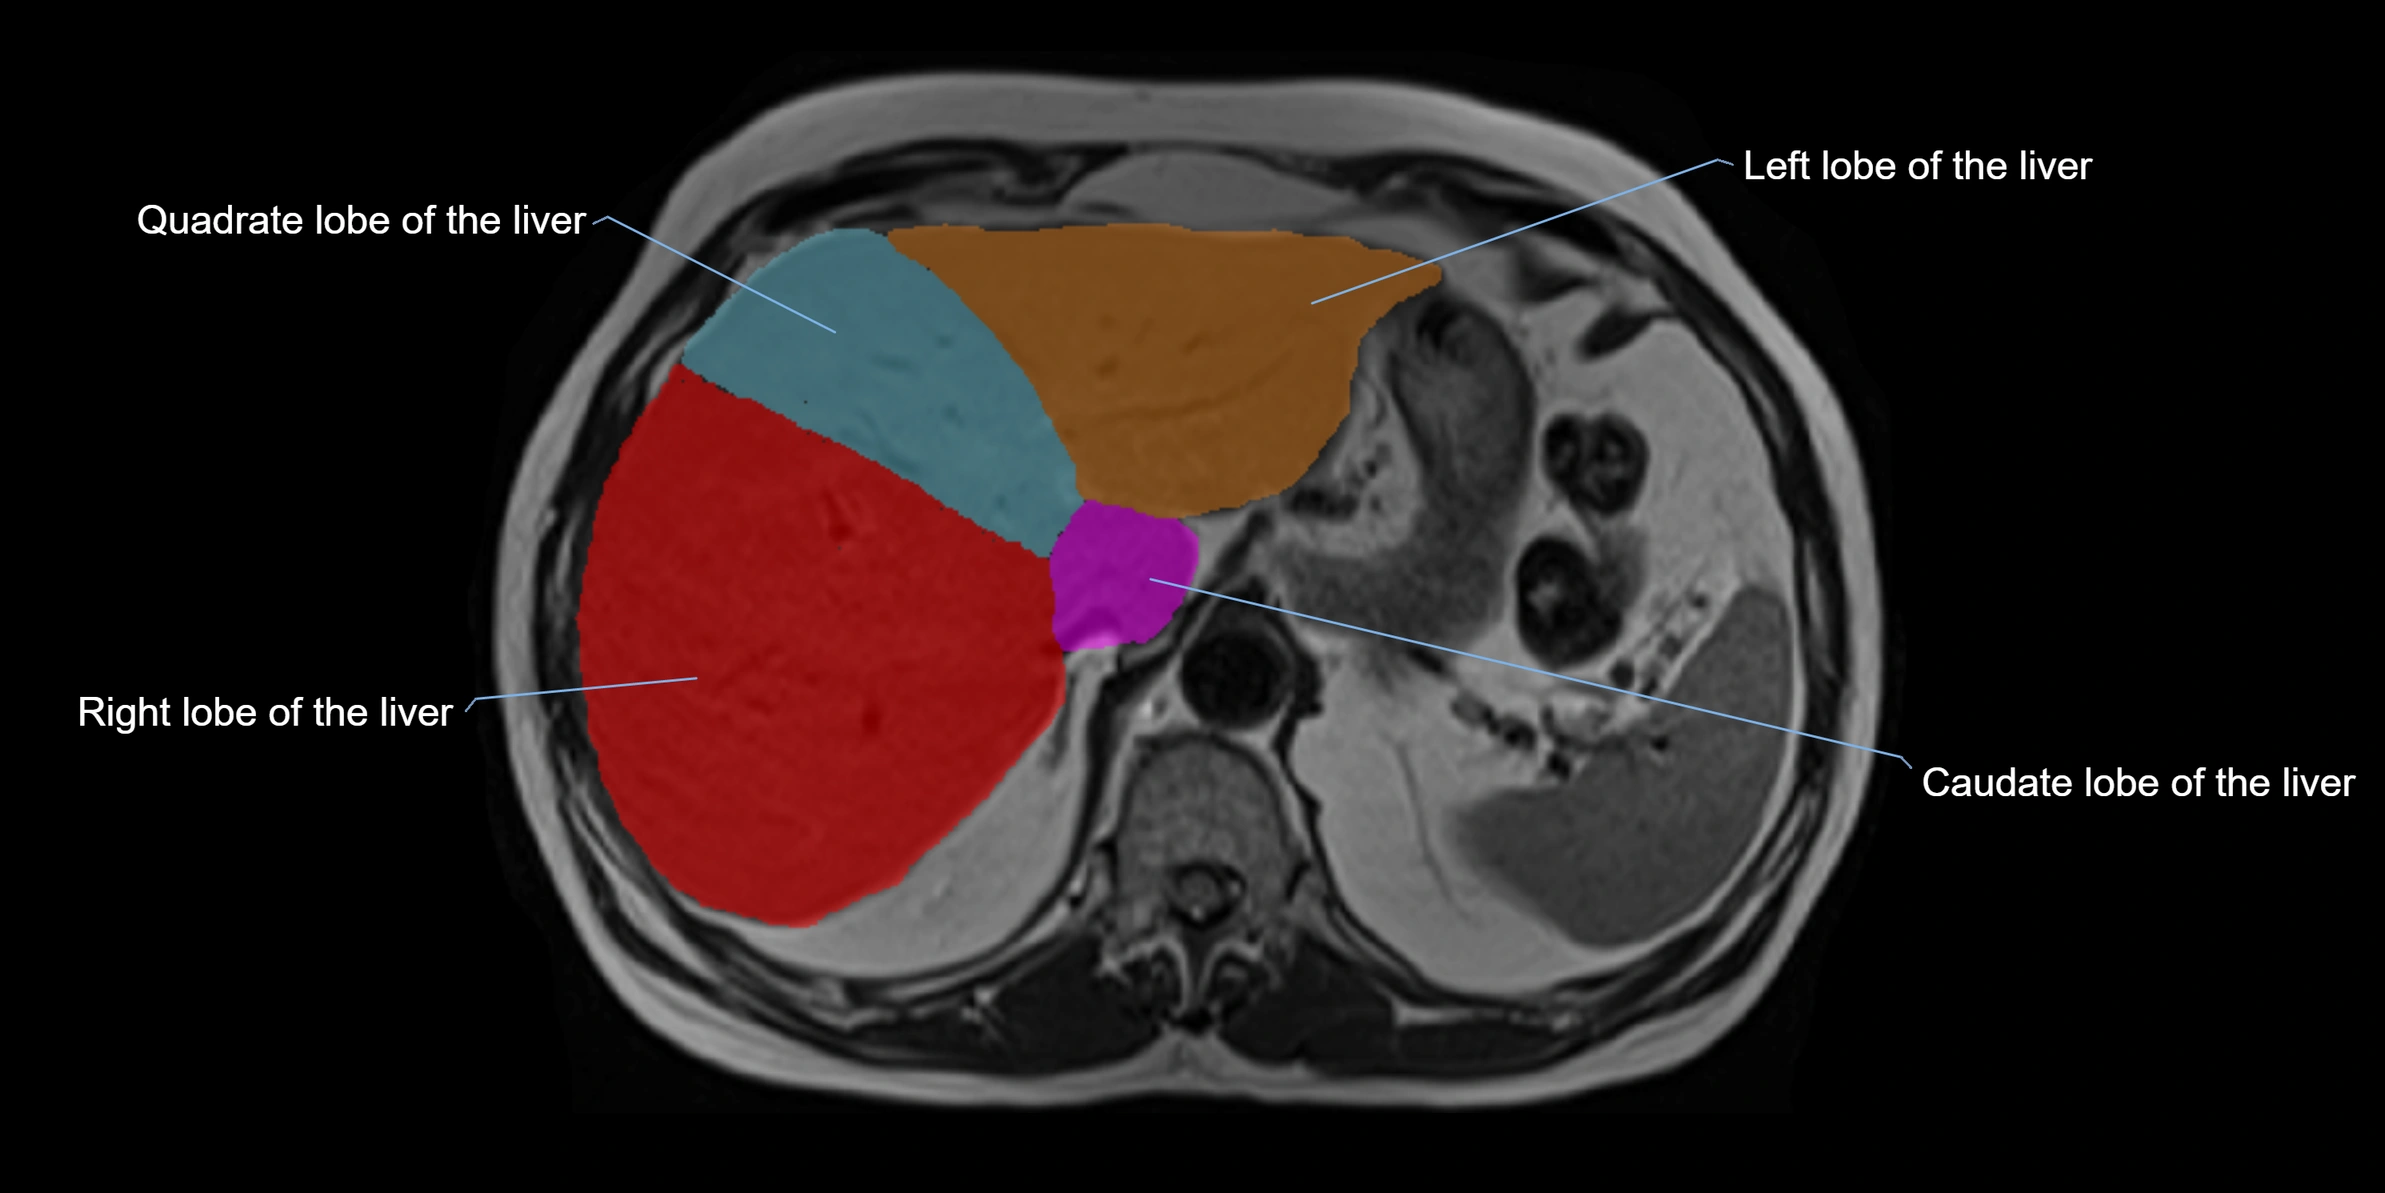

The caudate lobe of the liver is a distinct anatomical subdivision of the liver, designated as segment I in Couinaud’s classification. It lies on the posterior surface of the liver, between the fissure for the ligamentum venosum (left boundary) and the groove for the inferior vena cava (IVC) (right boundary). Superiorly, it is related to the posterior liver surface, and inferiorly it is separated from the left lobe by the porta hepatis.

The caudate lobe is unique because it receives dual portal venous and arterial inflow from both the right and left portal veins and hepatic arteries. It also has independent venous drainage directly into the IVC via multiple small hepatic veins, unlike other lobes that drain through the three main hepatic veins.

This anatomical autonomy makes the caudate lobe especially significant in liver surgery, transplantation, and hepatic venous outflow obstruction syndromes (e.g., Budd–Chiari syndrome). Enlargement of the caudate lobe is a characteristic imaging feature in chronic liver disease and cirrhosis.